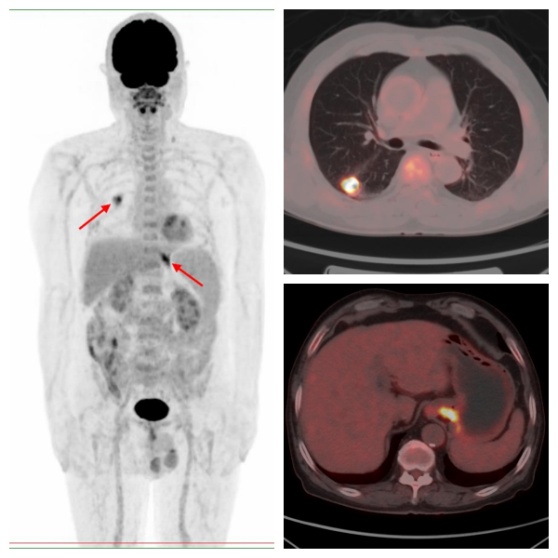

病例1,PET/CT示右肺下葉、賁門代謝異常,符合雙原發(fā)癌;之后患者行CT引導(dǎo)下肺部病變穿刺,病理證實(shí)原發(fā)肺腺癌,行胃鏡下賁門病變活檢,病理證實(shí)原發(fā)賁門腺癌。